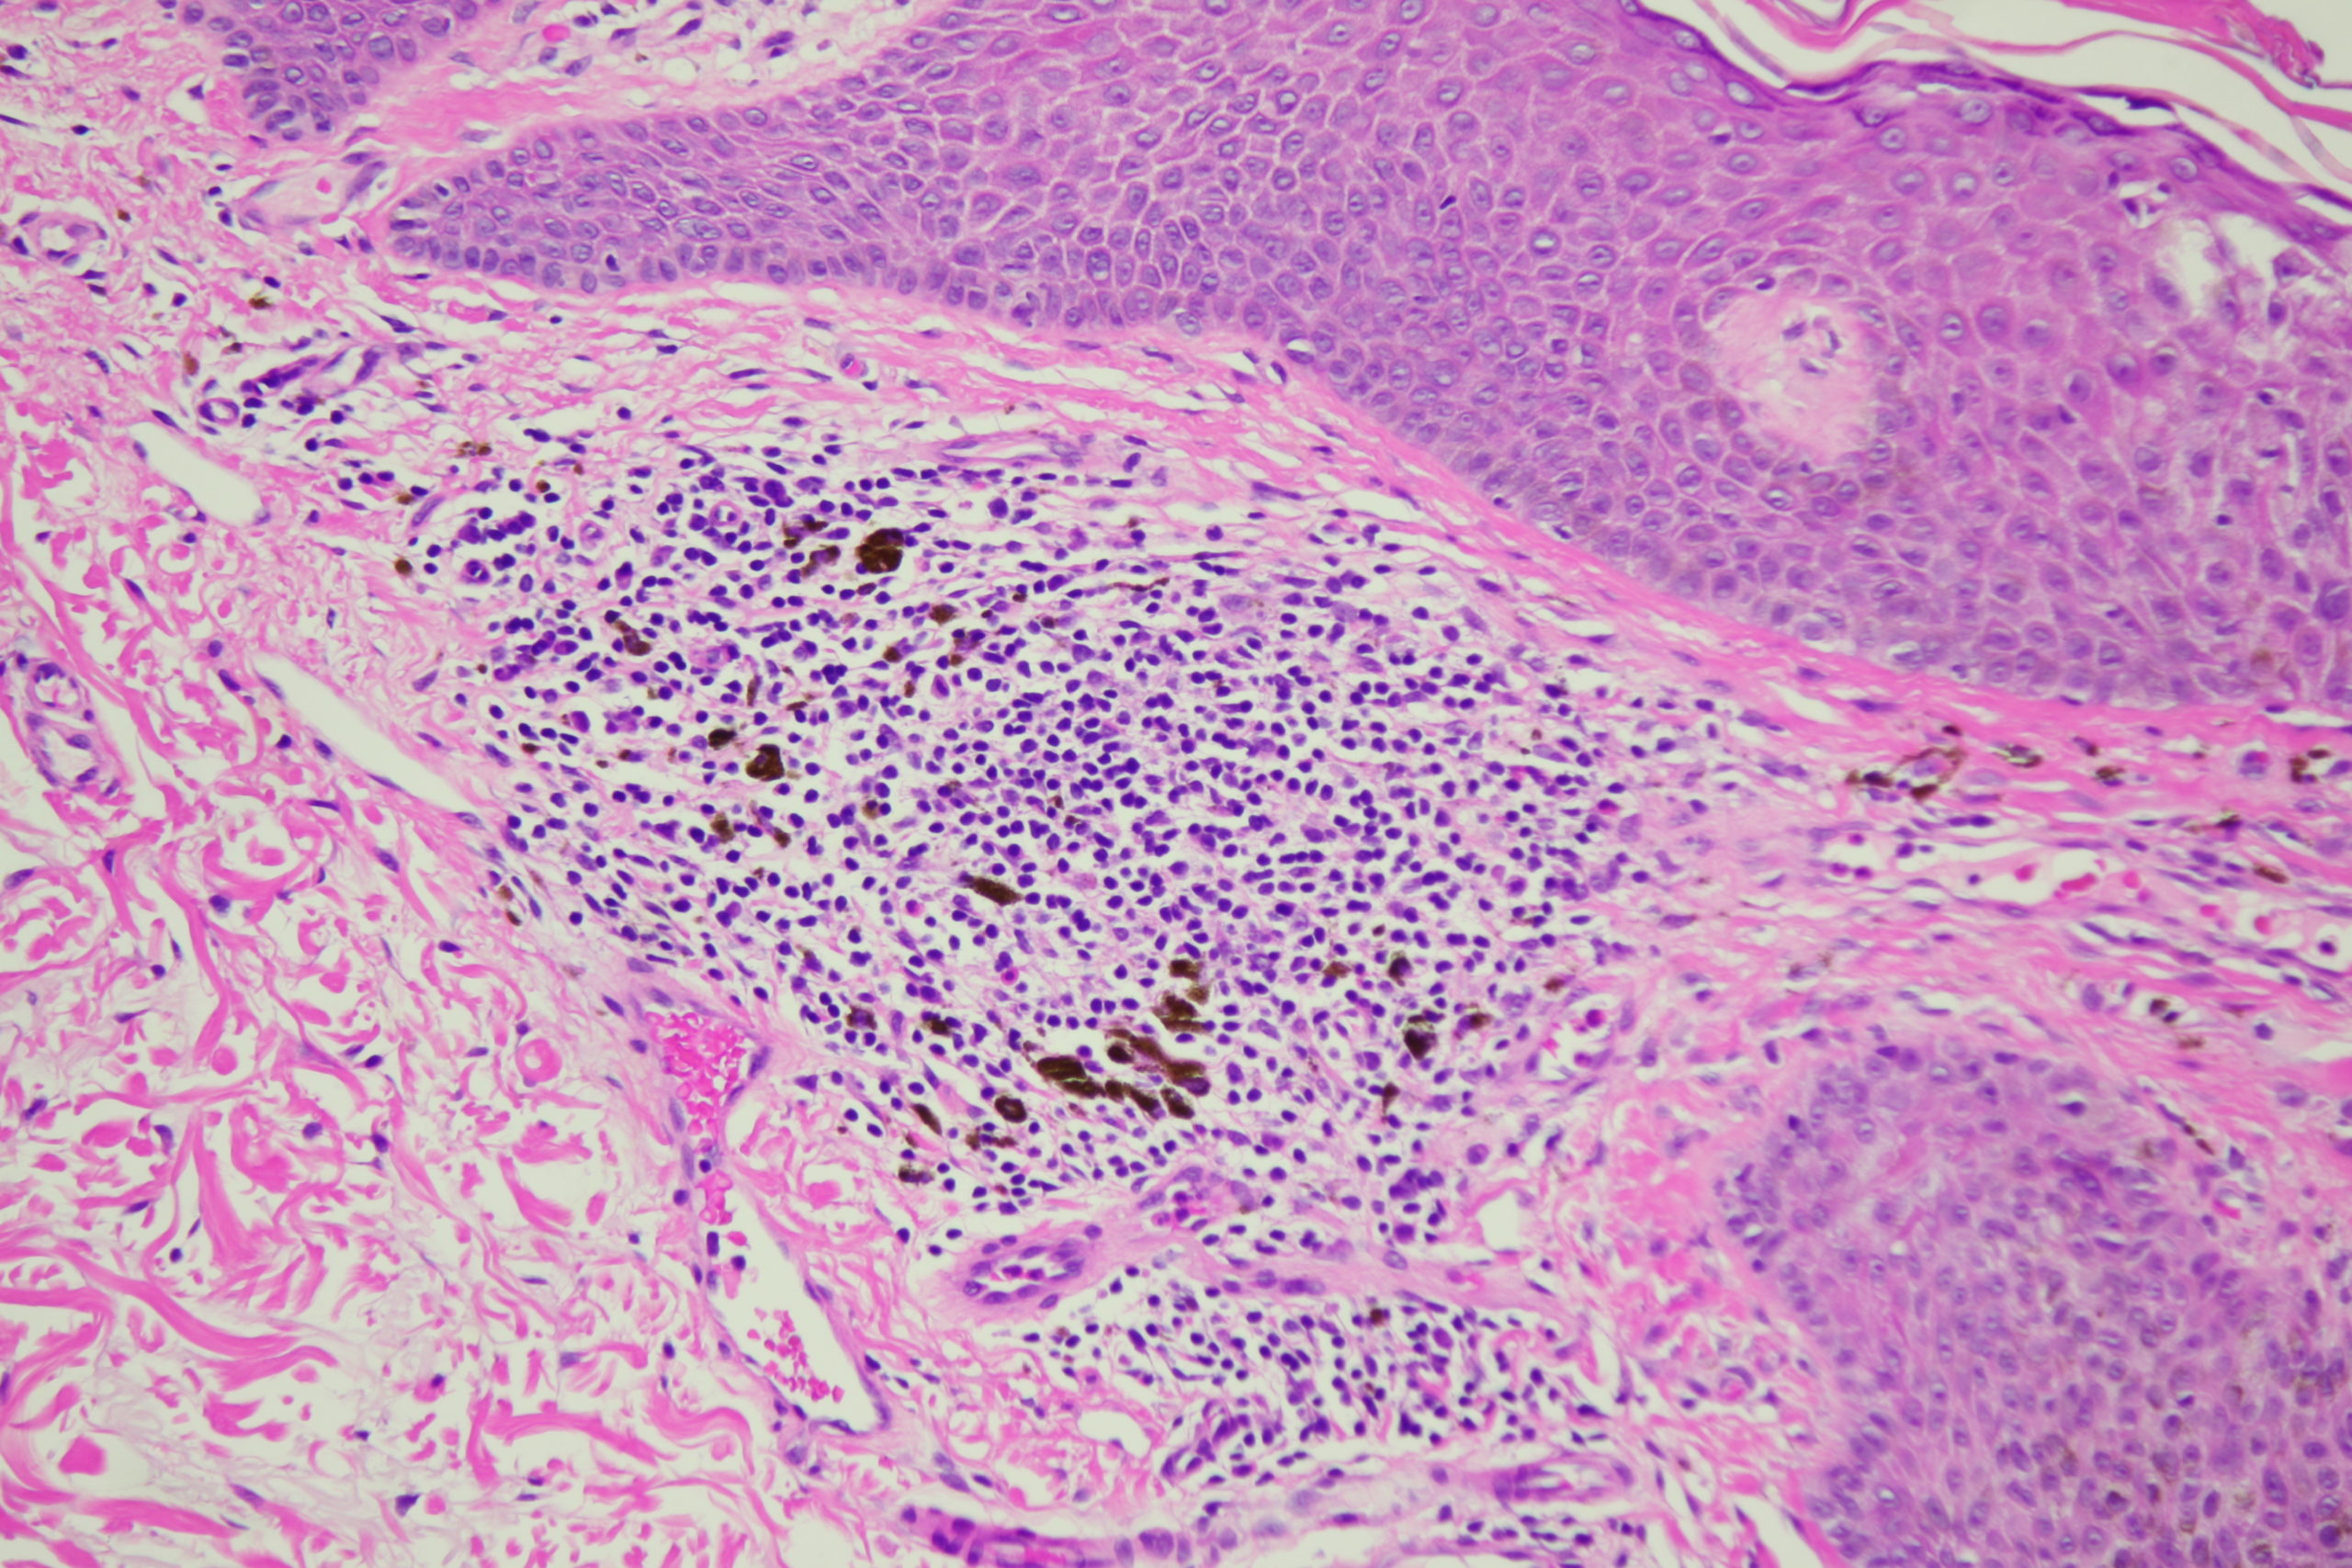

Site: Back

Diagnosis: Seborrhoeic keratosis irritated

Age: 72

Description: Dark blue blackish structureless areas surrounding paler center and white surface scales Broad coarse fatty brownish radial circumferential structures and black dots

A man in his 70s with this pigmented lesion on his upper back noted during a skin check.I look carefully at all dark seb k like lesions because lentigo maligna can easily involve a seb k. However I am always concerned about missing a seb k like melanoma. What do you think of this one? Note the pink colour surrounding it.